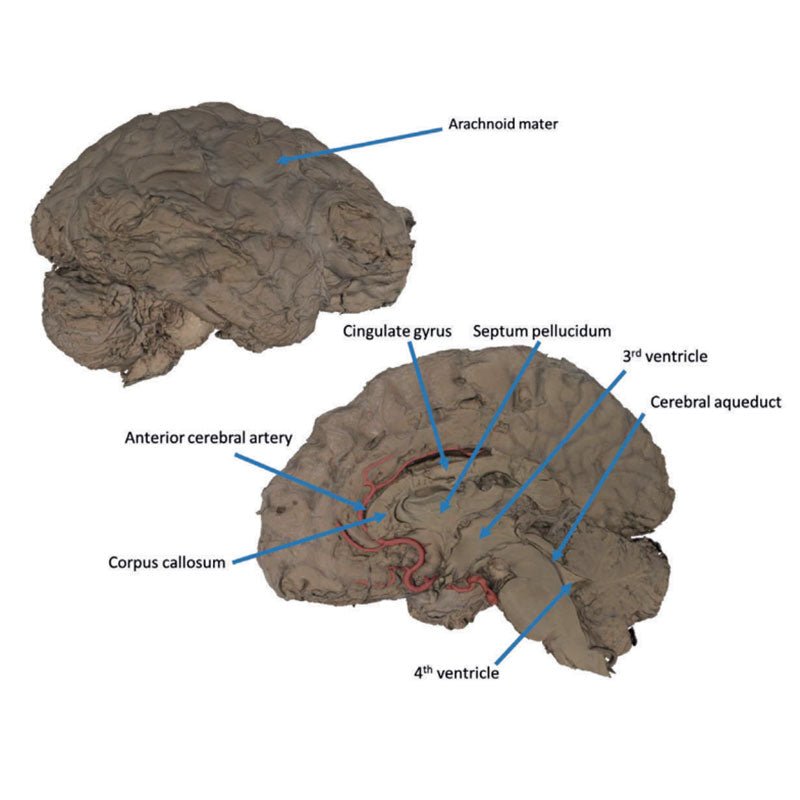

This 3D model is a midsagittal hemisection through a whole brain, preserving the right side anatomy and deep brain

structures and spaces visible in the midline. In lateral view, the right cerebral and cerebellar hemispheres are

covered in the arachnoid mater. In the midline view, the brain regions from the cerebrum to the medulla oblongata

are preserved. Centrally, the third ventricle is opened, with an intact septum pellucidum superiorly positioned and

obscuring the lateral ventricles within the cerebral hemisphere. On the inferior margin of the third ventricle both

the right mamillary body and right optic tract can be observed, whereas posteriorly the cerebral aqueduct can be

observed extending across the midbrain between the tectum and tegmentum towards the fourth ventricle (between the

cerebellum and pons). The cerebellum is separated from the occipital lobe by a preserved portion of the tentorium

cerebelli, and in cross-section the cerebellar cortex helps form the prominent arbor vitae.

A series of arterial

branches have been false coloured to contrast their course across the preserved brain structures. In the midsagittal

view the anterior cerebral artery courses from around the corpus callosum to supply the cingulate gyrus and other

midline cortical regions. The base of the middle cerebral artery can be seen passing deep between the temporal and

frontal lobes, with the posterior communicating artery connecting it to a small remnant of the posterior cerebral

artery. Adjacent to the posterior cerebral is the superior cerebellar artery, extending laterally to pass between

the temporal lobe and the cerebellum before passing deep into the transverse fissure.